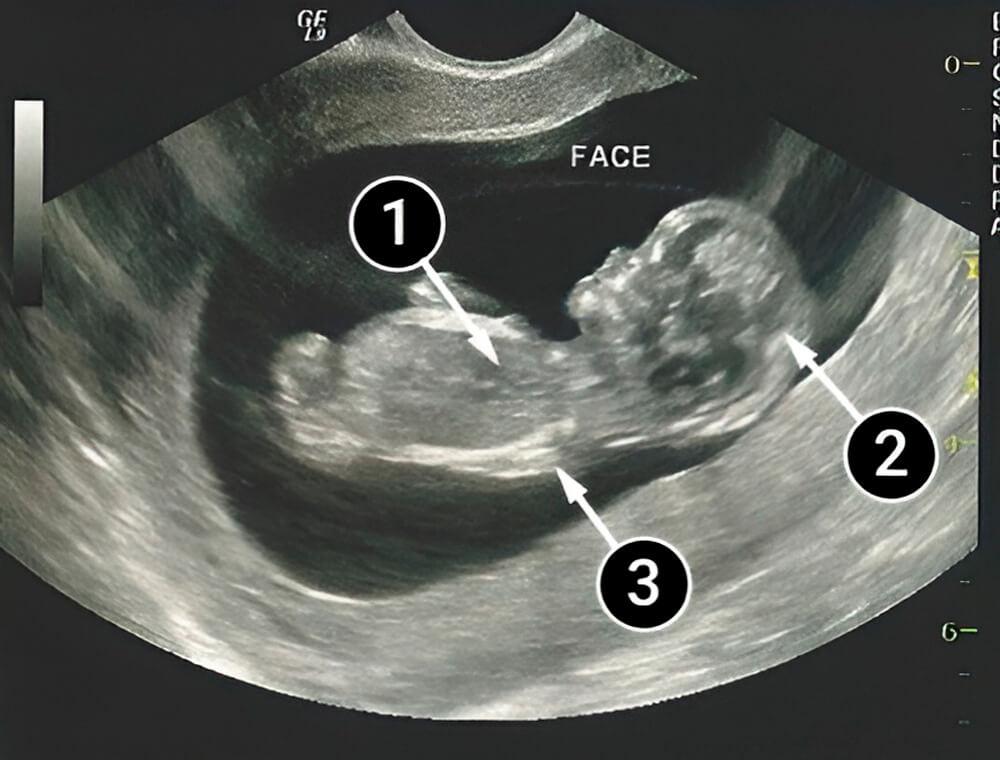

La primera fotografía muestra a un bebé acostado boca arriba rodeado de líquido amniótico. Sus movimientos se vuelven más definidos, pues ya puede alejarse de la pared del útero.

La cabeza del bebé es claramente visible, ahora representa casi la mitad de su cuerpo.

Las partes de la cara están claramente delineadas: la nariz, las mejillas y, en el espacio entre ellas, es visible la boca.

En primer plano se encuentran el hombro y el brazo izquierdo del bebé. Mientras que las piernas están dobladas y no se visualizan.

La mancha oscura en el tórax es el corazón, el cual ya tiene 4 cámaras, pero la sangre venosa y la arterial aún se mezclan.

corazón

cabeza

mano